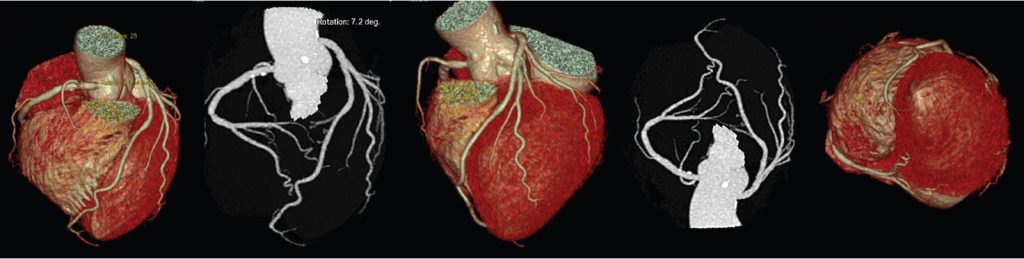

A CT Scan or Computed Tomography Scan is a diagnostic imaging technique that uses a series of X-rays to create detailed images of the inside of the body. It is more sophisticated and detailed than a standard x-ray as it is able to visualise a lot more details of the internal organs and structures that are not visible through a standard x-ray. CT scans are able to generate detailed images of organs, blood vessels, muscles, bones, and fat.

However, in case of a CT scan, there is a motorised x-ray source that rotates in a circular motion around the tunnel inside the scanner. As the x-ray source rotates, it shoots narrow x-ray beams through the patient’s body. The CT scanner has digital x-ray detectors that capture the rays as they leave the patient’s body. The detected rays are then transmitted to the computer where it generates the images.

When the x-ray source completes one rotation, the computer generates a 2D image slice which is stored. The bed on which the patient lies then moves into the cavity in small increments. Every time the x-ray source makes one complete rotation, it transmits the detected rays to the computer where it generates another image slice.

Once the required number of image slices have been achieved, the images are displayed individually or combined together to create a 3D image of the organ or structure. These slices of images allow the doctor to effectively locate the source of a disease or problem.